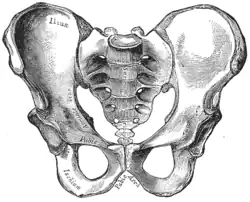

Traditional obstetrical services relied heavily on pelvimetry in the conduct of delivery in order to decide if natural or operative vaginal delivery was possible or if and when to use a cesarean section.[9] Women whose pelvises were deemed too small received caesarean sections instead of birthing naturally.

Traditional obstetrics have characterized four types of pelvises:

- Gynecoid: Ideal shape, with round to slightly oval (obstetrical inlet slightly less transverse) inlet.

- Android: triangular inlet, and prominent ischial spines, more angulated pubic arch.

- Anthropoid: the widest transverse diameter is less than the anteroposterior (obstetrical) diameter.

- Platypelloid: Flat inlet with shortened obstetrical diameter.